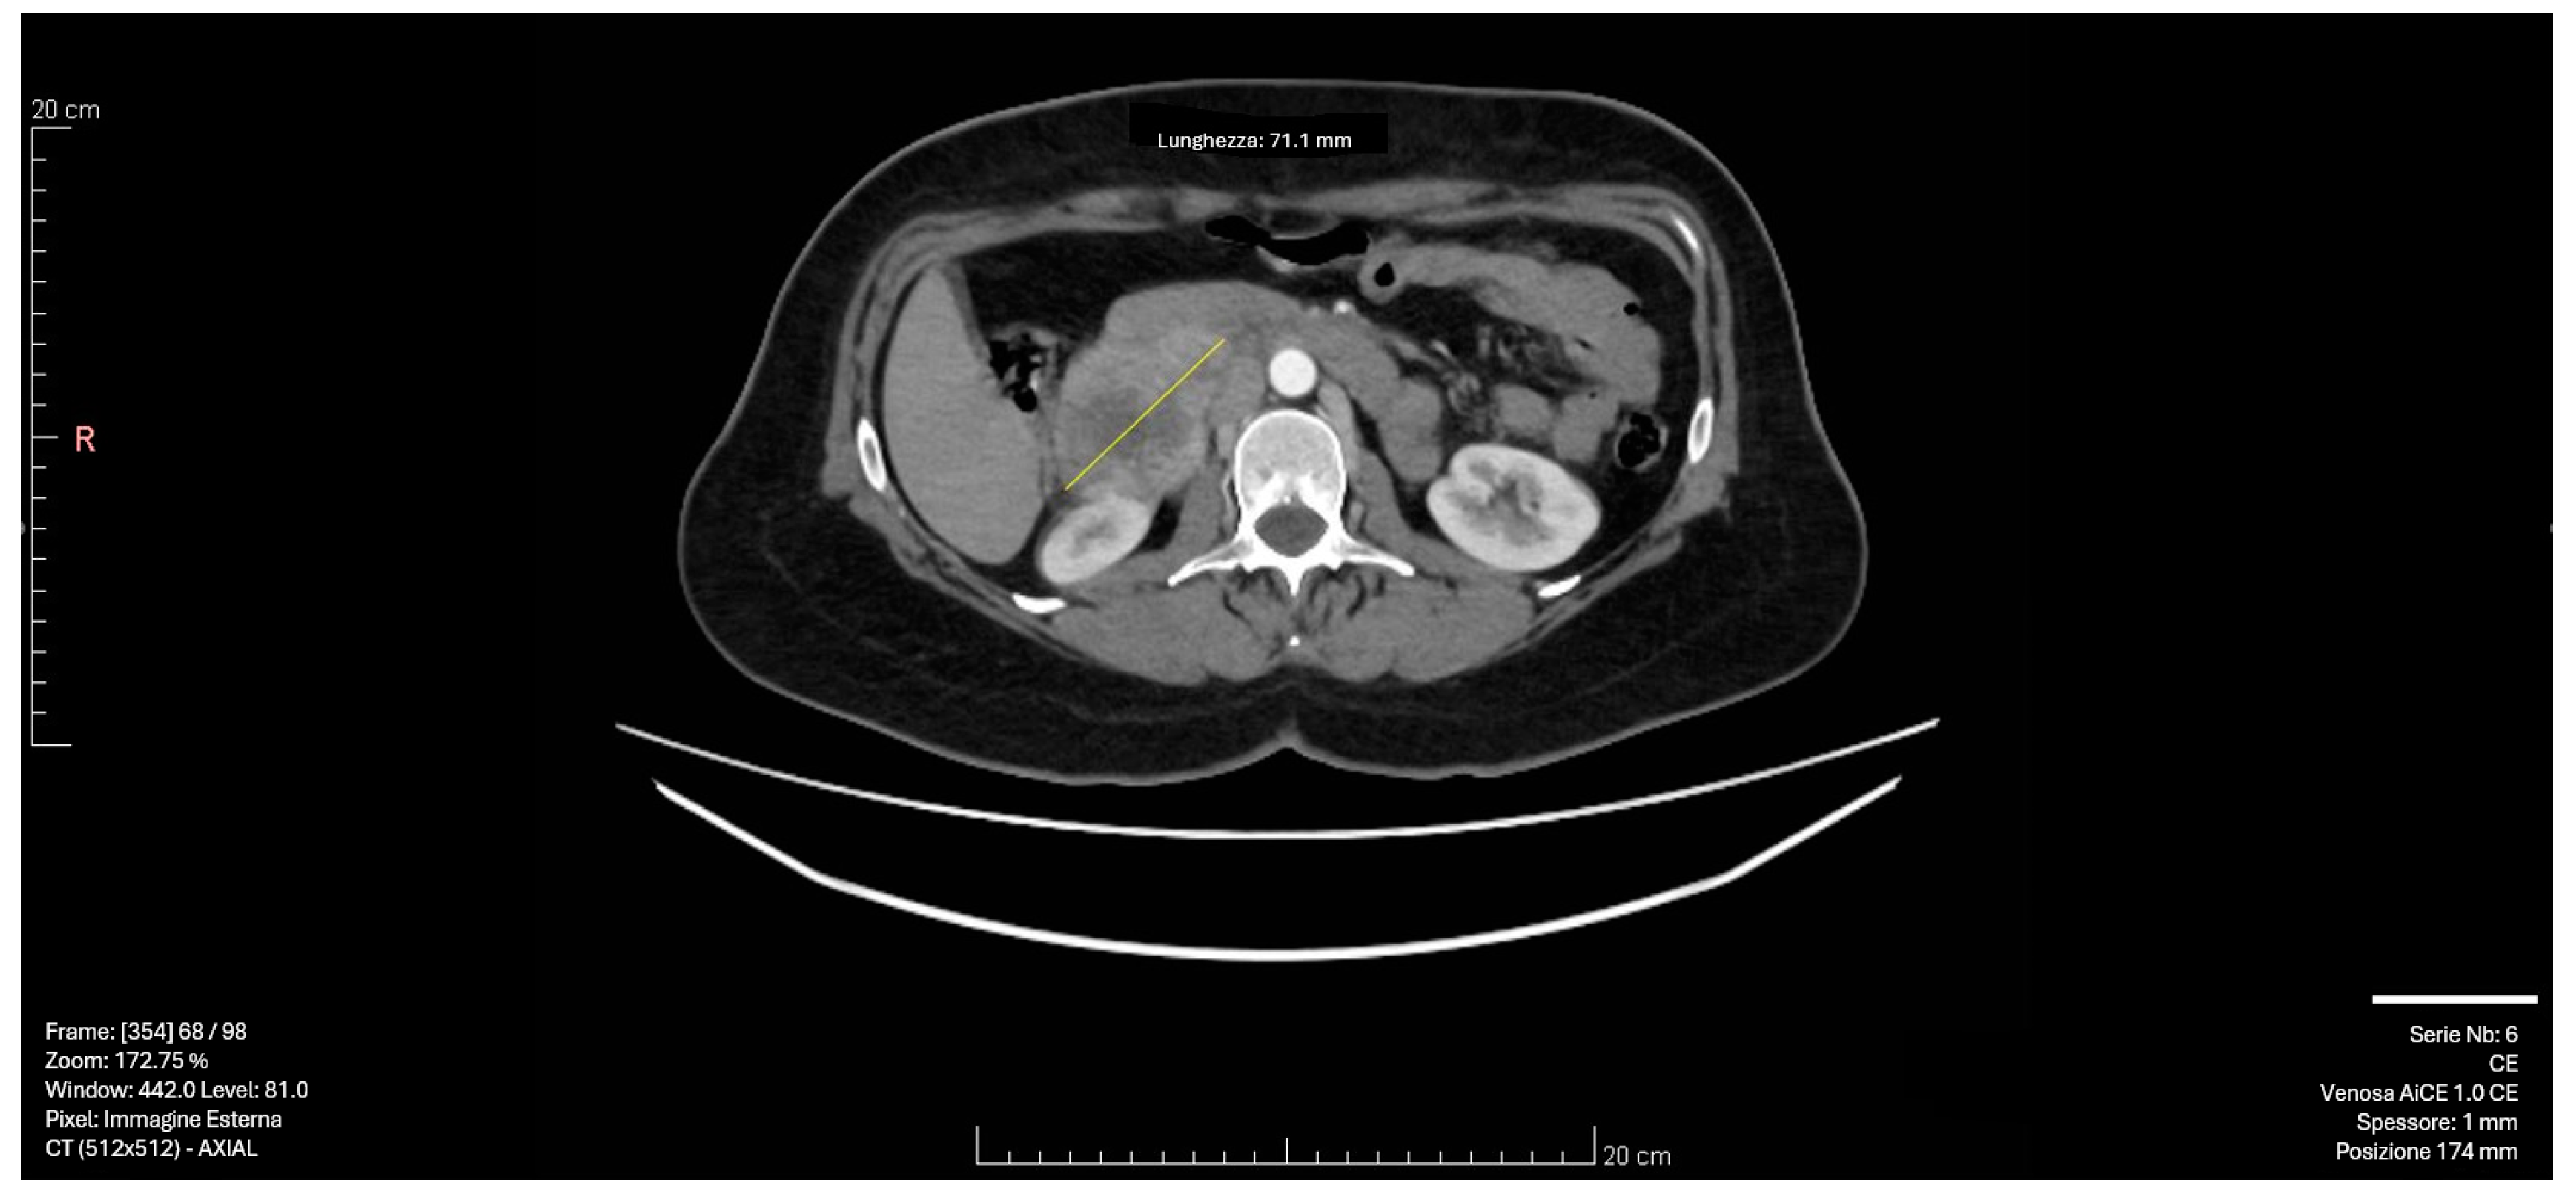

Subsequent CT imaging with intravenous contrast revealed a 55 × 50 mm solid formation with a necrotic core and irregular peripheral enhancement in the right adrenal lodge. The mass demonstrated adjacency to but no infiltration of the inferior vena cava, with venous drainage observed in the right ovarian vein. The left adrenal gland appeared normal, with no significant lymphadenopathy [Figure 1].

Figure 1.

CT scan image: The right adrenal mass demonstrated adjacency to but no infiltration of the inferior vena cava, with venous drainage observed in the right ovarian vein. The yellow arrow indicates the 55 × 50 mm solid formation with a necrotic core and irregular peripheral enhancement in the right adrenal lodge.